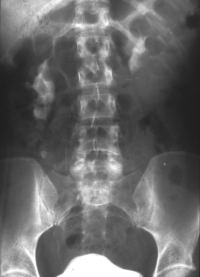

Rechtsseitige Ureterabgangsstenose mit deutlicher Hydronephrose. Behandlung mit Ureterabgangsplastik nach Anderson-Hynes (Abbildung 19).

• Abbildung 19:

1. Rechtsseitige Ureterabgangsstenose mit deutlicher Hydronephrose